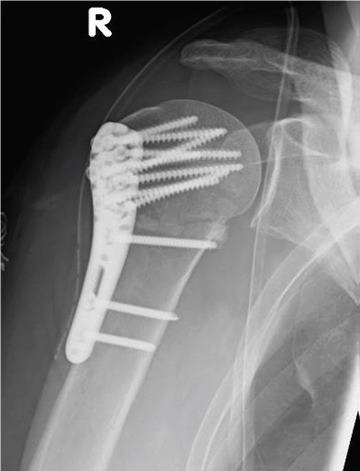

Während bei jüngeren Patienten die Rekonstruktion von Knochen und Gelenken im Vordergrund steht, führt bei älteren Patienten häufig der Gelenkersatz zur schnelleren Wiederherstellung der Beweglichkeit.